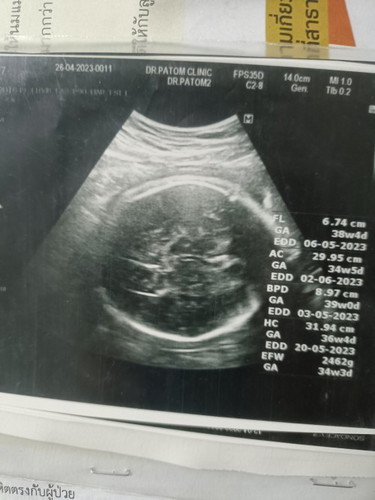

น้อง34w5d น้ำหนัก2500กรัม

หมอบอกเตรียมตัวรอได้เลย น้องพร้อมออกมาทุกเวลา

ตัวใหญ่มากเลยค่ะ